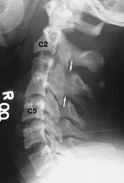

| Prior imaging | oldest & most recent |

| Bodies | Height, trabeculations |

| Disks | Height, |

| Odontoid | #'s, dens-anterior arch distance (adults: < 3 mm; peds: < 5 mm) |

| Lines | Anterior spinal line, posterior spinal line, spinolaminar line, clivus base line |

| Lordosis | |

| Soft tissue swelling | Retropharyngeal, retroesophageal |

| Degenerative disk disease (DDD) | ↓ disk space osteophytes borders of adjac vert bodies may vacuum phen |

| DISH | flowing ossifn >= 4 contig verts no facet or SIJ ankylosis rel minimal DDD |

| Spondylosis deformans | ant & lat osteophytes rel preserved disk spaces |

| Facet DJD | osseous facet overgrowth ↓ jt space sclerosis |

Facet DJD + DDD may → degen spondylolisthesis